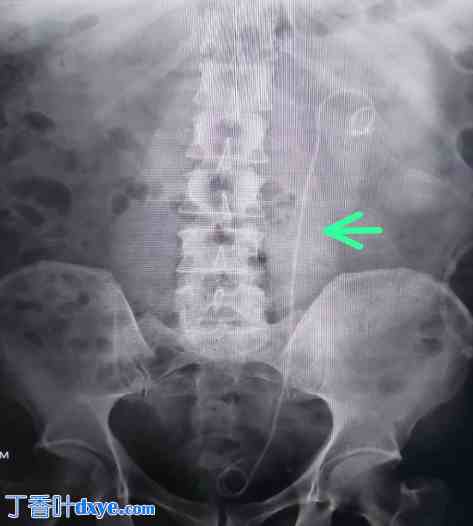

一名63岁男性,无已知合并症,因左侧腰痛及下尿路症状六个月就诊。放射学检查显示左肾结石(如图1、2和3所示),提示需要进行经皮肾镜取石术(PCNL)。患者接受了经皮肾镜取石术(PCNL),并置入DJ支架用于术后引流(如图4所示)。此外,还置入了肾造瘘管用于引流。

图1

术前CT扫描。

术前X光片显示左肾结石。